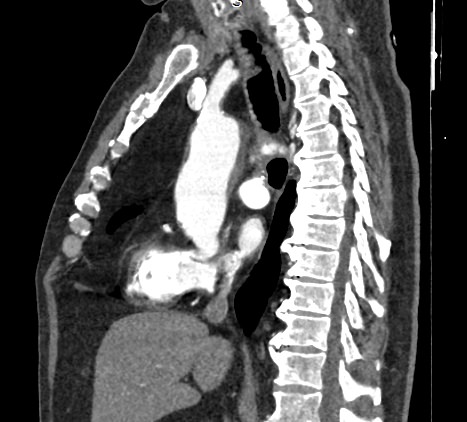

В брюшной полости и забрюшинном пространстве расположены группы лимфатических узлов, которые окружают внутренние органы (желудочные, печеночные, брыжеечные, чревные, подвздошные и др) и располагаются вдоль крупных кровеносных сосудов. Лимфоузлы относятся к периферическим органам иммунной системы человека и выполняют защитную функцию, являясь барьером для проникновения инфекций и задерживают распространение раковых клеток.

Патологические изменения регионарных лимфоузлов часто свидетельствуют о поражении того органа, от которого происходит лимфоотток. Это имеет важное значение для оценки распространенности онкологического процесса, выявления отдаленного метастатического поражения лимфатической системы, а также используется для определения тактики лечения. Кроме того, патология лимфатических узлов может говорить о развитии гемобластозов и лимфопролиферативных заболеваний крови.

Компьютерная томография позволяет детально визуализировать структуру лимфатических узлов, выявить ее неоднородность, гиперплазию, определить деформацию контуров, появление инфильтрации окружающих тканей с образованием пакетов и конгломератов лимфоузлов.

С целью повышения контрастности изображений, выявления патологических изменений в лимфоузлах дополнительно внутривенно вводится рентгеноконтрастное вещество на основе йода. Контраст накапливается в патологических очагах и под воздействием рентгеновских лучей обусловливает их яркое изображение на фоне неизмененной ткани. Контрастирование значительно повышает диагностическую ценность исследования и помогает выявлять многие серьезные заболевания на начальных этапах.

Что показывает КТ лимфоузлов с контрастом

• гиперплазия,

• неоднородность,

• пакеты, конгломераты лимфоузлов,

• изменения контуров,

• инфильтрация окружающих тканей,

• жировая ткань ворот узла,

• сдавление прилежащих органов, сосудов.

• уплотнение клетчатки, наличие жидкости.

• новообразование